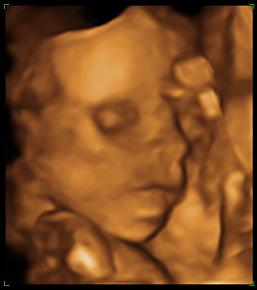

Kép babalak a 22. héten

Honey formás kicsi fiú lapul a pocidban, ááá dehogy lapul csodásan kerekedik az a lak!

Honey: Szépen megmutatta magát a fiatalember, hogy szopizza a kis kezét, nagyon aranyos :)